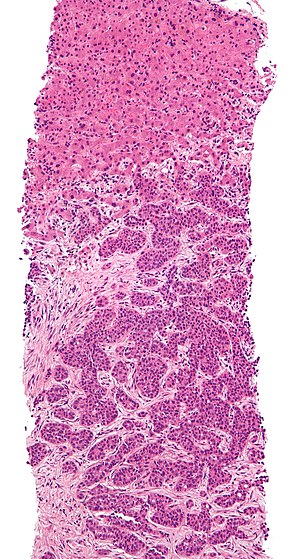

Micrograph of a liver core needle biopsy showing cancer.